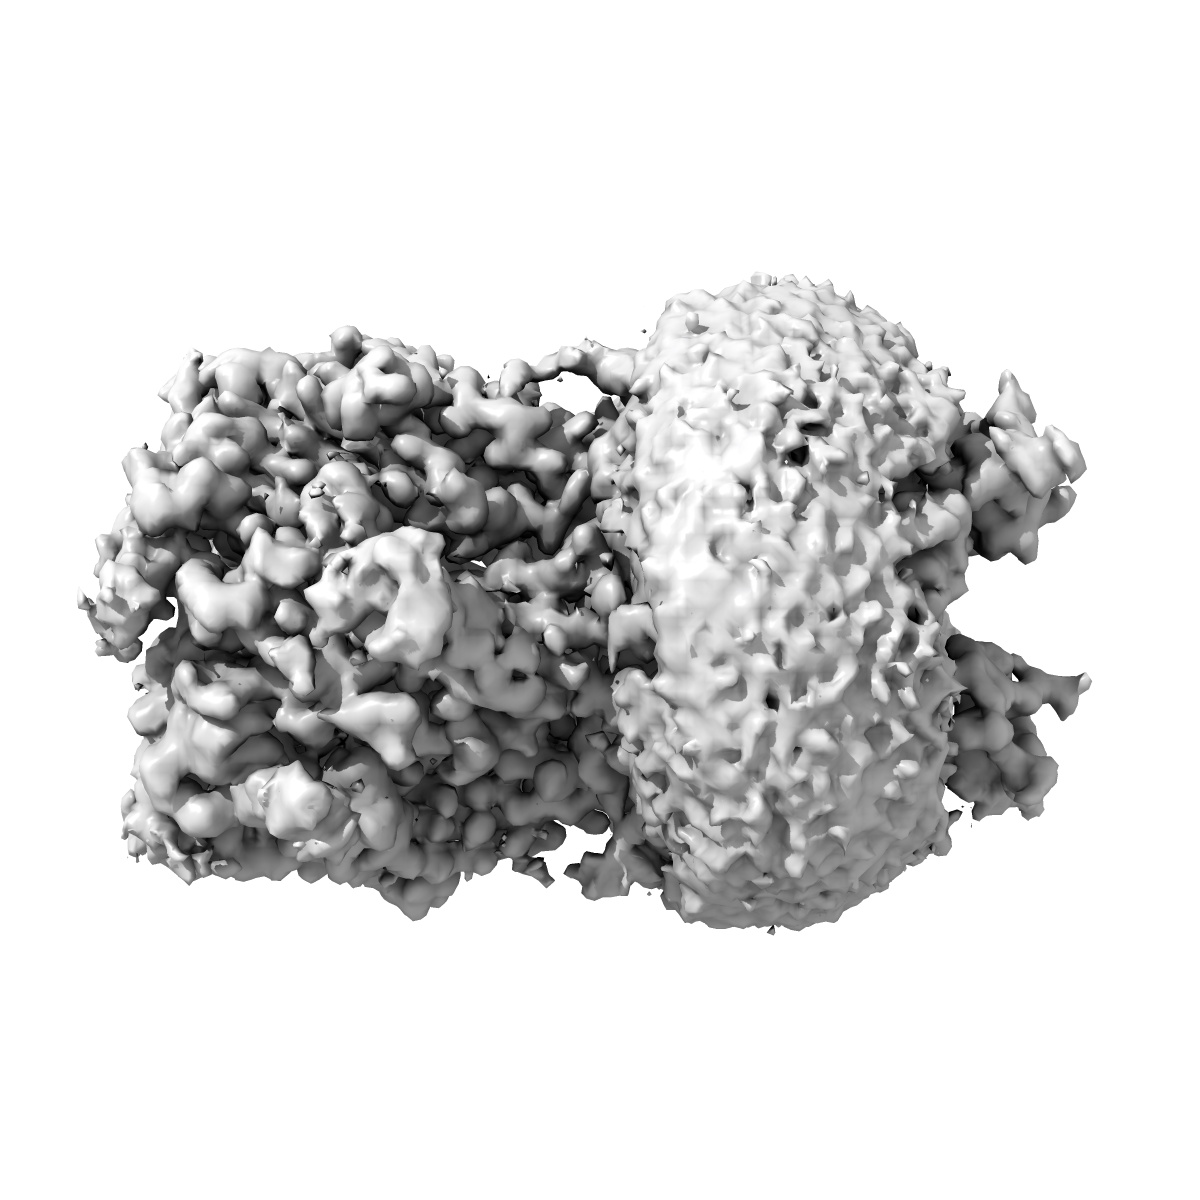

Cryo-EM structure of the full-length alpha1beta3gamma2 GABA(A) receptor in complex with GABA in the short-lived symmetric bound-closed state

Sample: Cryo-EM structure of the full-length alpha1beta3gamma2 GABA(A) receptor in complex with GABA in the short-lived symmetric pre-active state

Cryo-EM structure of the full-length alpha1beta3gamma2 GABA(A) receptor in complex with GABA in the short-lived symmetric pre-active state